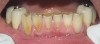

Figure  4  Possibly a combination of erosion and abrasion.

Figure 4

Characteristics of damage to tooth structures caused by acidity include wear on the occlusal surfaces of molars and a saucer shape on the cusps of molars (perimolysis).12 The erosion can vary from minor and subtle changes on the tooth surface, ie, loss of luster, a dull or matted look, to cupping on occlusal surfaces or incisal edges, which may extend to dentin. Usually, the erosive lesions demonstrate greater width than depth. When combined with abrasive forces or stresses, the tooth surface loss may occur at a faster rate (Figure 2, Figure 3, Figure 4 and Figure 5).